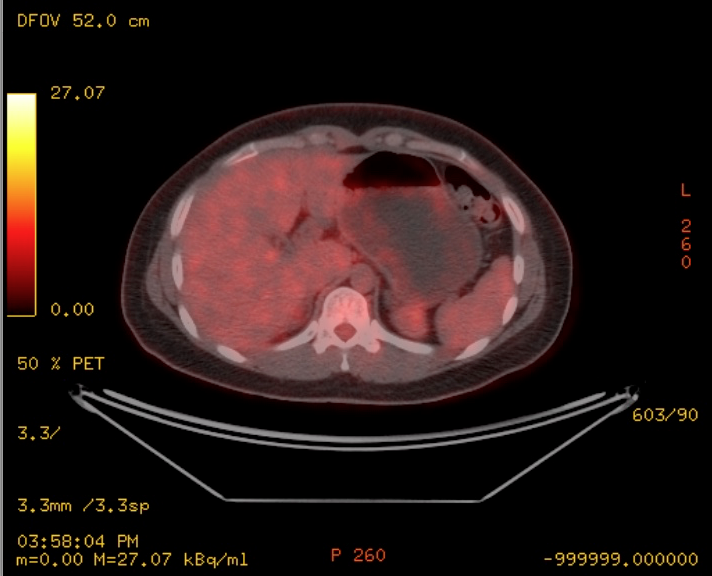

Mujer de 57 años.

Cuadro clínico de 1 mes de evolución caracterizado por distensión abdominal e hiporexia.